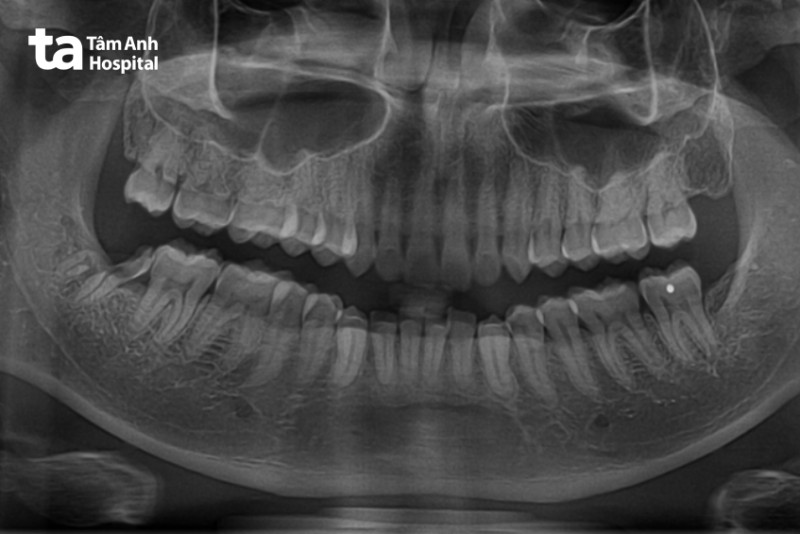

Viêm tủy xương là một trong những biến chứng của việc nhổ răng khôn, trong vài trường hợp có thể bị nhầm với viêm huyệt ổ răng. Dấu hiệu nhận biết là người bệnh sốt, đau và sưng tấy ở vùng vừa nhổ răng. Nếu các triệu chứng kéo dài hơn một tháng, người bệnh nên đi khám và chụp X-quang để được chẩn đoán chính xác có bị viêm tủy xương hay không. Viêm tủy xương đòi hỏi phải điều trị lâu dài bằng thuốc kháng sinh cho đến khi khỏi bệnh.

Khi thực hiện nhổ răng khôn tại cơ sở uy tín như chuyên khoa Răng Hàm Mặt, Bệnh viện Đa khoa Tâm Anh TP.HCM, người bệnh sẽ được chẩn đoán hình ảnh bằng cách chụp X-quang, chụp CT để cải thiện độ chính xác cũng như an toàn hơn cho người bệnh.